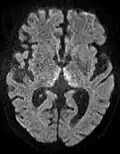

ADC image of the same case of cerebral infarction as seen on DWI in section above

An apparent diffusion coefficient (ADC) image, or an ADC map, is an MRI image that more specifically shows diffusion than conventional DWI, by eliminating the T2 weighting that is otherwise inherent to conventional DWI.[24][25] ADC imaging does so by acquiring multiple conventional DWI images with different amounts of DWI weighting, and the change in signal is proportional to the rate of diffusion. Contrary to DWI images, the standard grayscale of ADC images is to represent a smaller magnitude of diffusion as darker.[23]

Cerebral infarction leads to diffusion restriction, and the difference between images with various DWI weighting will therefore be minor, leading to an ADC image with low signal in the infarcted area.[24] A decreased ADC may be detected minutes after a cerebral infarction.[26] The high signal of infarcted tissue on conventional DWI is a result of its partial T2 weighting.[27]